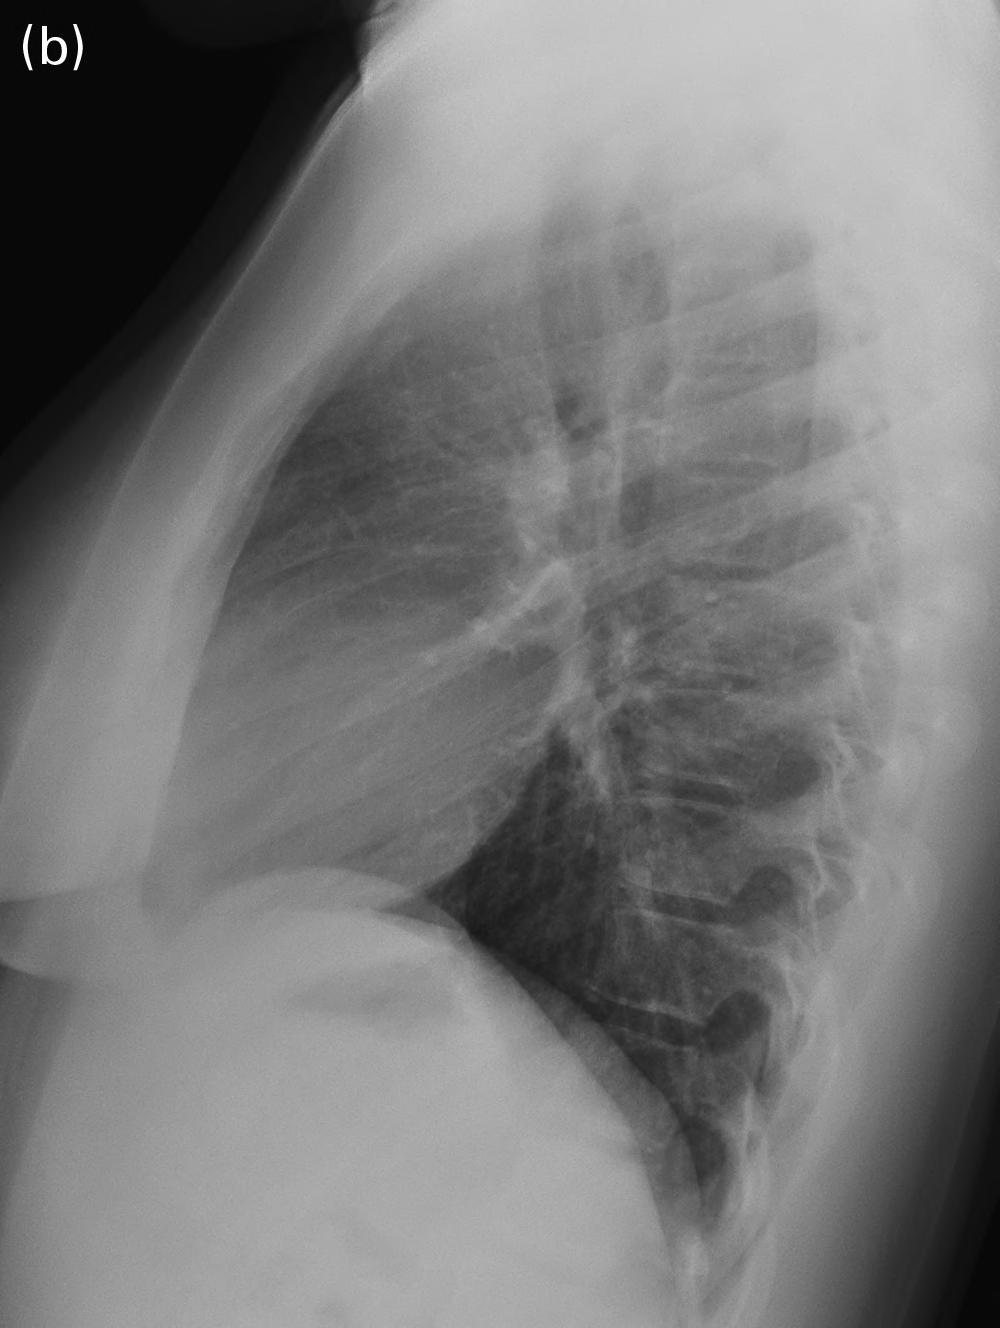

The clinicians for this patient started with a chest radiograph. The initial chest radiographic identified small pleural effusions and interlobular septal thickening, which were suggestive of interstitial pulmonary edema (see Figures 1.1a and 1.1b). Findings become more apparent when compared with a normal 16-year-old’s chest radiographs (Figures 1.2a and 1.2b). Because of the patient’s vomiting, an abdominal film was also obtained, which demonstrated significant cardiomegaly (see Figure 1.1c), thus leading to the diagnosis of dilated cardiomyopathy and/or pericardial effusion. On the chest radiograph, the reduced lung volumes and elevated hemidiaphragms masked the cardiomegaly, which was more apparent on the better penetrated abdominal radiograph.

Careful attention to the heart, mediastinum, airway, lungs, pleura, bones, and soft tissues is essential to accurately diagnose the cause of chest pain. A screening chest film for patients with chest pain has low sensitivity for structural cardiovascular lesions, such as myocarditis, dissection, or pulmonary infarction, but is helpful in the acute setting to diagnose complications of underlying cardiovascular conditions, such as HF, mediastinal hematoma, or pulmonary infarction. It is also helpful to exclude noncardiac causes of chest pain, including pneumonia, pneumothorax, rib fracture, or an aspirated foreign body (see normal chest radiograph, Figures 1.2a and 1.2b).

FIGURES 1.2 a AND 1.2 b PA and lateral views of the chest in a normal 16-year-old for comparison (different patient). Note the normal appearance of structures. Contour of descending aorta (white arrowheads), superior mediastinal width between superior vena cava on the right and aortic arch on the left (white thick arrows on right and left side), tracheal air column (black arrow), carina (black arrowhead), and the orientation of the clavicles (thin white arrows). In a properly positioned patient the spinous processes lie midway between the medial ends of the clavicles. The cardiothoracic ratio is measured as the ratio of the cardiac transverse diameter (black thin line) divided by the maximum chest transverse diameter (thick black line). The first and second ribs on the left side are numbered (1, 2).